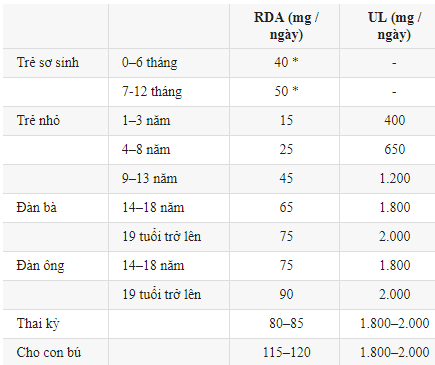

RDA chưa khuyến nghị cho trẻ sơ sinh, Thay vào đó, bảng hiển thị lượng tiêu thụ phù hợp, được đánh dấu bằng dấu (*) là uống đầy đủ.

Những giá trị trên đại diện cho lượng hàng ngày đủ để đáp ứng yêu cầu của hầu hết mọi người.

Bảng trên đây cho thấy RDA hoặc lượng niacin đủ dùng. Những giá trị này là lượng niacin ước tính mà hầu hết mọi người (97,5%) cần nhận được từ chế độ ăn uống hàng ngày. UL – là lượng tiêu thụ hàng ngày cao nhất được coi là an toàn đối với hầu hết mọi người.

RDA là lượng tiêu thụ hàng ngày được ước tính là đủ đối với hầu hết mọi người. UL – là lượng tiêu thụ hàng ngày cao nhất được coi là an toàn đối với hầu hết mọi người.

RDA là lượng tiêu thụ hàng ngày được ước tính là đủ đối với hầu hết mọi người.

RDA là lượng tiêu thụ hàng ngày được ước tính là đủ đối với hầu hết mọi người. UL – là lượng tiêu thụ hàng ngày cao nhất được coi là an toàn đối với hầu hết mọi người.